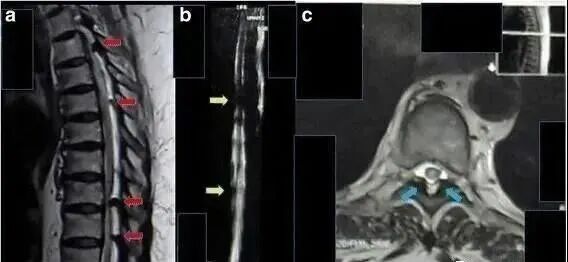

2017年11月,国际期刊《Journal of Medical Case Reports》上曾发表了一篇题为“Improvement of renal function after human umbilical cord mesenchymal stem cell treatment on chronic renal failure and thoracic spinal cord entrapment: a case report”的临床研究报告。

图片

此项研究中,科研团队收治了一位62岁印度尼西亚裔女性患者,患者因患有糖尿病影响肾脏,慢性肾功能衰竭2年,肌酐水平为11mg/dl,此后无排尿。科研人员在进行评估后决定采用间充质干细胞进行治疗。

该方案包括鞘内植入1.6*10∧7个脐带间充质干细胞和静脉植入1.6*10∧7个脐带间充质干细胞。第一次鞘内和静脉植入三周后,患者可以移动脚趾,肾脏功能得到改善。其肌酐水平下降至9mg/dl。8个月后,患者可以抬起双腿,肌酐水平为2mg/dl,排尿正常。